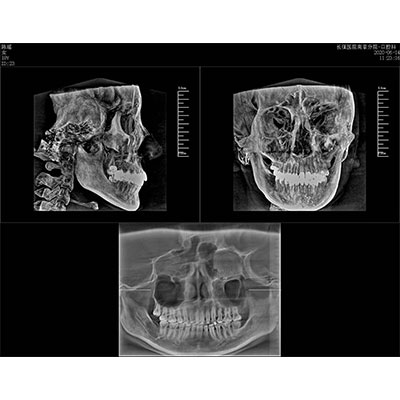

高清口腔三維CT/全景影像 PLX3000A

該款牙科CBCT產(chǎn)品采用動(dòng)態(tài)平板探測(cè)器,獲得三維圖像的同時(shí)還具有數(shù)字化全景功能,廣泛應(yīng)用于口腔頜面外科、正畸科、正頜外科、種植科、牙體科、顳下頜關(guān)節(jié)科等術(shù)前術(shù)后。

專有三維重建算法,可提供任意位置高清斷層影像。

通過三維容積影像,提取高清口腔全景影像。

可同時(shí)觀察軸向面、冠狀面和矢狀面圖像,方便臨床診斷。